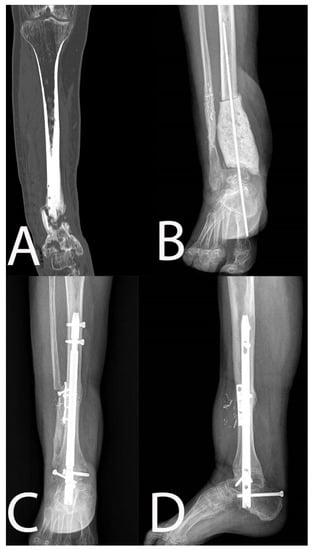

| 10 | 58, M | 3 | No | 5 | Yes | Type 4 | Type 4 Bl |

| 10 | Resection | No | 100 | MSSA | ALT | 34 | No | ||

| 9 | 59, M | 2 | No | 4 | Yes | Type 4 | Type 4 Bl |

| 9 | Resection | Yes | 100 | MRSA + P. aeruginosa + E. faecalis | ALT | 30 | No | ||